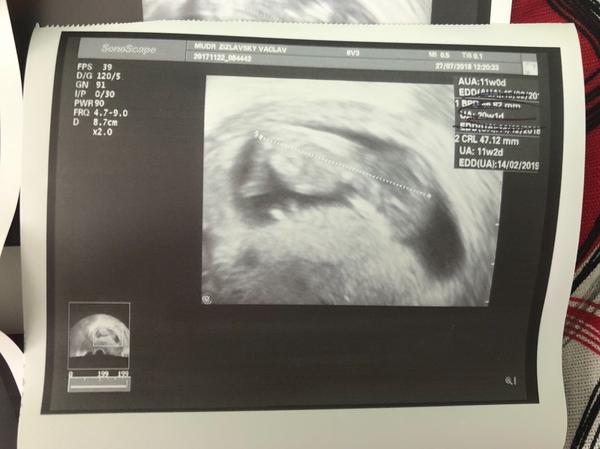

Tak jsem doma. Nakonec jsem skoncila s ANTB Protoze mam v cevkovane moci bílé krvinky celkem dost pry. Takze nejspis silný zanet. Od ceho to muze byt mi nerekl Protoze Ja jen polehavam doma. Takze ač nerad tak musel nasadit šetrné antibiotika. A Ja mam stale pochybnosti s tim je vubec brat. Nemáte rady jak to obejít ??? Jinak na UTZ vse v poradku. Dokonce jsme povyrostli o 2,5cm za 10dni. A TP se nam změnilo na Valentýna.